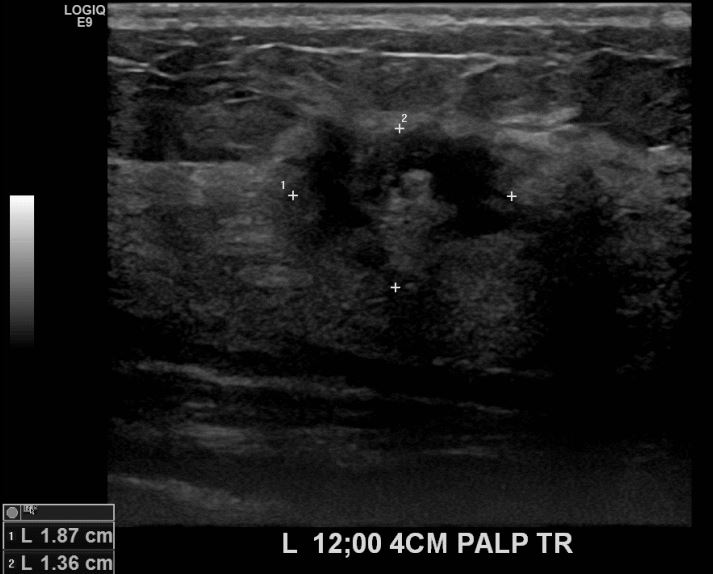

상기환자 좌측유방멍울만져져 내원하신 30대 여성분으로 유방암 의심혹 조직검사 시행 후 유방암 진단되었습니다.